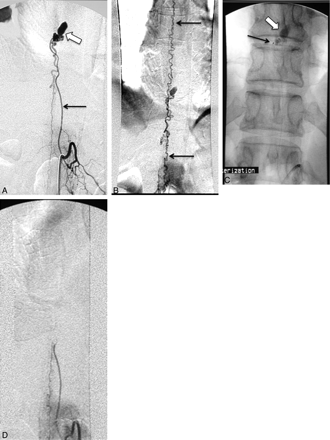

A, Epidural AVM supplied by the left T7 intercostal artery (arrow). Note the venous drainage into dilated epidural veins (block arrow). B, Selective angiogram via a microcatheter placed into the arterial feeder shows no supply to the ASA or PSA. C, The AVM is embolized with n-BCA with the glue cast shown in the unsubtracted image.

A, A 69-year-old man with progressive bilateral lower extremity weakness. Sagittal T2-weighted MR image shows intramedullary edema in the lower thoracic spine and the conus medullaris (arrow) with flow voids surrounding the cauda equina and conus medullaris (arrowheads), consistent with venous hypertension. B, Catheter angiogram shows an AVF in the sacral region (block arrow), supplied by the iliolumbar arteries bilaterally (arrows). C, The arteriovenous shunt drains into the sacral epidural veins (arrowheads, B and C), which in turn communicate with dilated spinal veins (arrows), causing venous hypertension. D, This epidural AVF is embolized with Onyx with obliteration of the feeding arteries, the arteriovenous shunt, and epidural veins. There is no residual communication with the spinal veins. E, MR imaging of the lumbar spine obtained 7 months after the embolization shows marked improvement of the intramedullary edema and perimedullary flow voids, correlating with near-complete resolution of the patient's symptoms.